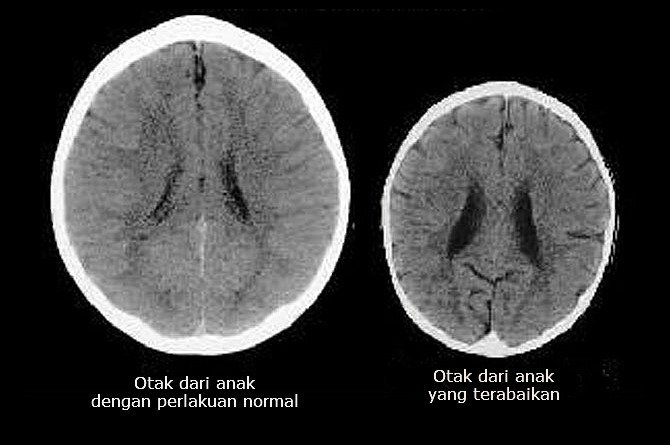

Ibu ayah, cuba perhatikan kedua-dua gambar otak di bawah ini.

Selain saiznya yang berbeza, gambar otak di sebelah kiri juga ada kedutan dan tanda hitam yang lebih kurang berbanding gambar di sebelah kanan.

Ahli neurologis menafsirkan kedua-dua gambar tersebut, dan menemui satu perbezaan yang sangat mengejutkan dan luar biasa.

Gambar otak di sebelah kanan secara jelasnya memiliki kekurangan di beberapa bahagian dibandingkan dengan gambar di sebelah kiri.

Kekurangan tersebut menyebabkan anak anda tidak mungkin dapat berkembang sesuai dengan kapasiti yang mampu dilakukan oleh pemilik otak di gambar kiri.

Kekurangan ini juga menyebabkan pemilik otak di gambar sebelah kanan kurang cerdas, kurang mampu berempati kepada orang lain, malah mungkin juga menjadi penagih, atau terlibat dalam kes jenayah.

Penyebab utama yang menyebabkan perbezaan pada saiz otak tersebut adalah bergantung kepada bagaimana kedua-dua kanak-kanak yang berusia 3 tahun ini dilayani oleh ibunya.

Anak yang disayangi sepenuh hati dan sikap ibu yang selalu berusaha memenuhi keperluannya akan mengalami perkembangan otak yang maksimum.

Sementara, kanak-kanak pemilik otak di gambar sebelah kanan pula sering diabaikan dan diperlakukan dengan kasar oleh ibunya.

Layanan tersebut ditunjukkan dengan kadar kerutan dan pengecutan saiz otak.